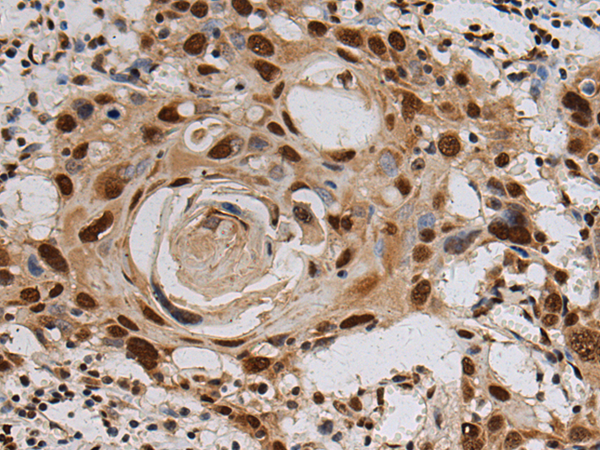

IHC positive control: |

Human esophagus cancer and Human tonsil |

IHC Recommend dilution: |

100-300 |